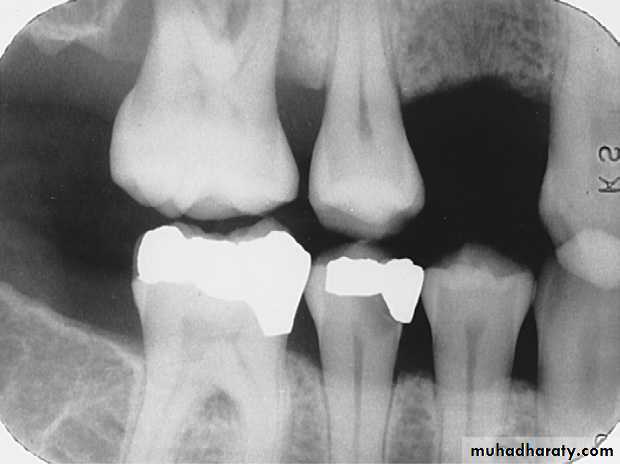

Recurrent Caries

Recurrent caries seen as a radiolucency below a two surface amalgam restoration on the mandibular second premolar.

Recurrent caries on upper first premolar